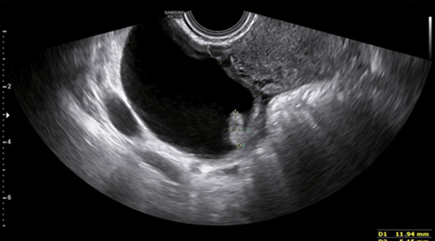

The left ovary showed a corpus luteal cyst (Figure 3). The findings were consistent with a twin intrauterine live dichorionic diamniotic pregnancy and a right ovarian pregnancy without cardiac activity.